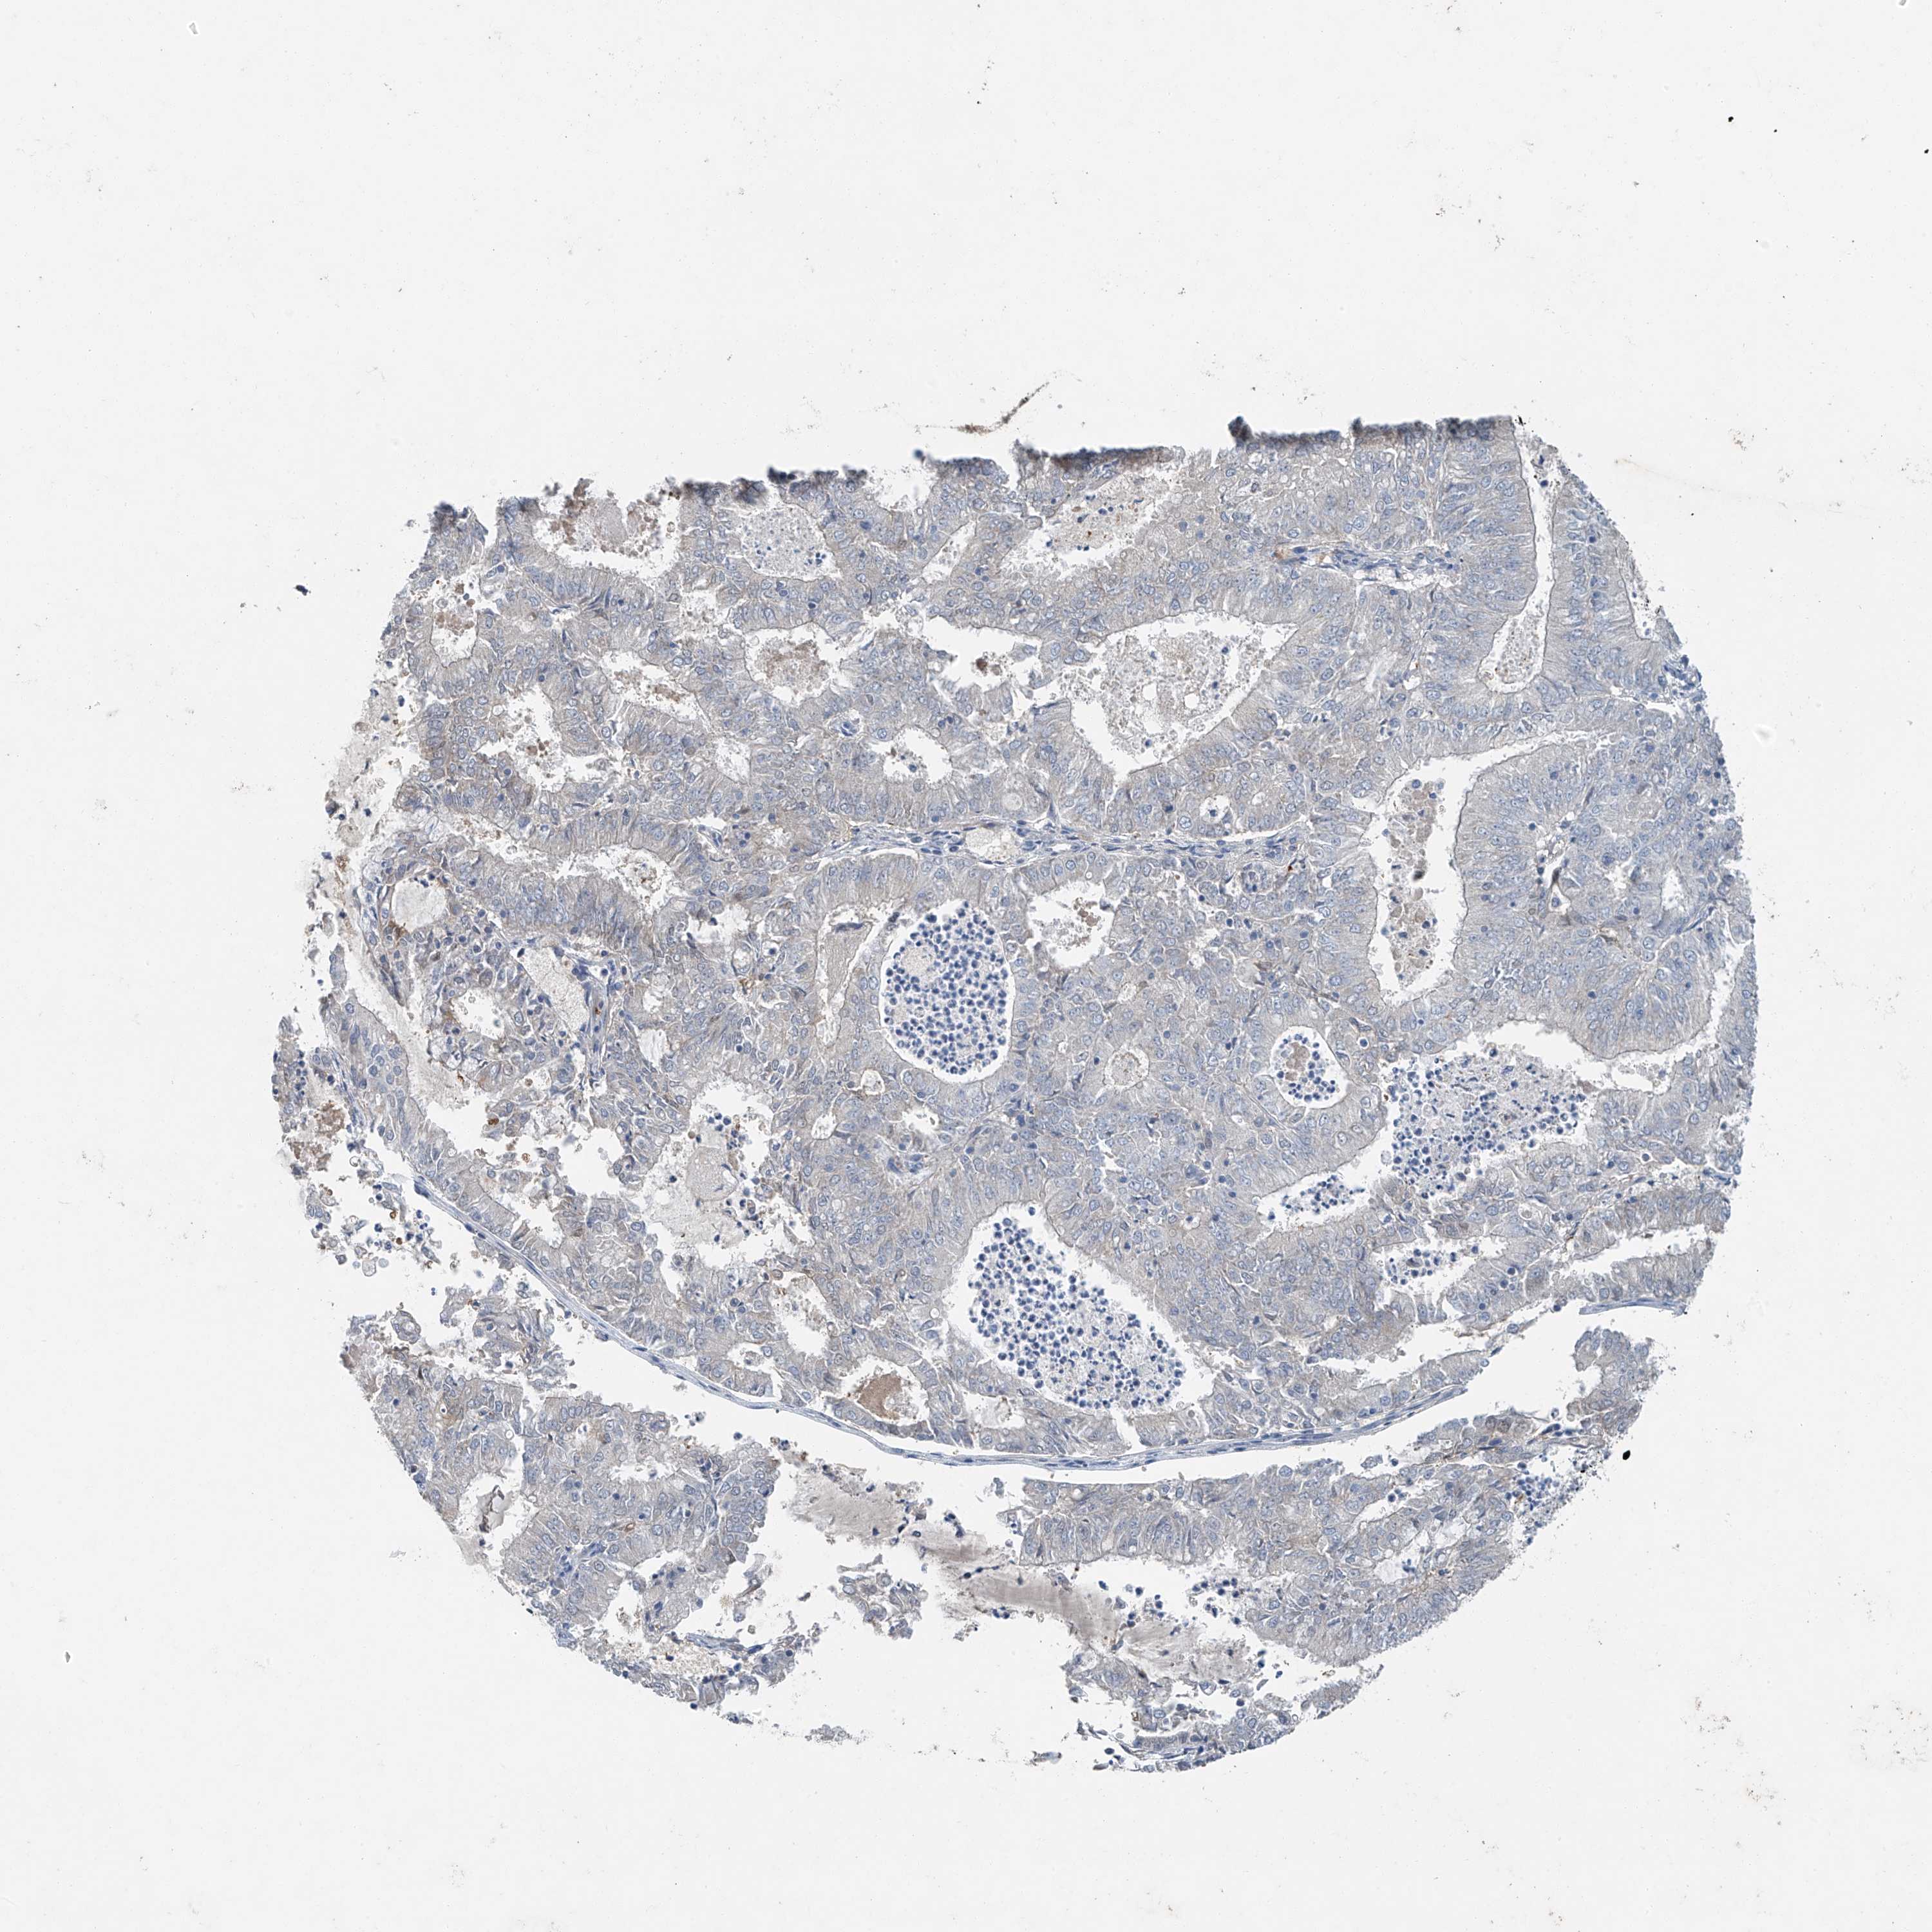

ENDOMETRIAL CANCER - Protein expressioni

A mouse-over function shows sample information and annotation data. Click on an image to view it in a full screen mode. Samples can be filtered based on level of antibody staining by selecting one or several of the following categories: high, medium, low and not detected. The assay and annotation is described here.

Note that samples used for immunohistochemistry by the Human Protein Atlas do not correspond to samples in the TCGA dataset.

Antibody stainingi

Antibody staining in the annotated cell types in the current human tissue is reported as not detected, low, medium, or high, based on conventional immunohistochemistry profiling in selected tissues. This score is based on the combination of the staining intensity and fraction of stained cells.

Each image is clickable and will lead to virtual microscopy that enables deeper exploration of all samples and also displays staining intensity scores, fraction scores and subcellular localization as well as patient and tissue information for each sample.

Antibody HPA031730

Antibody HPA031731

Antibody HPA031734

Staining

High

Medium

Low

Not detected

Intensity

Strong

Moderate

Weak

Negative

Quantity

>75%

75%-25%

<25%

None

Location

Nuclear

Cytoplasmic/membranous

Cytoplasmic/membranous,nuclear

Adenocarcinoma, NOS

Adenocarcinoma, metastatic, NOS